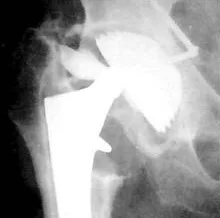

Как видно на приведенной рентгенограмме, после удаления эндопротеза остаётся "пустое место" в области бывшего тазобедренного сустава.

Это ведёт к децентрации головки эндопротеза (на представленной рентгенограмме видно смещение головки эндопротеза от центра) и нарушению функции конечности.